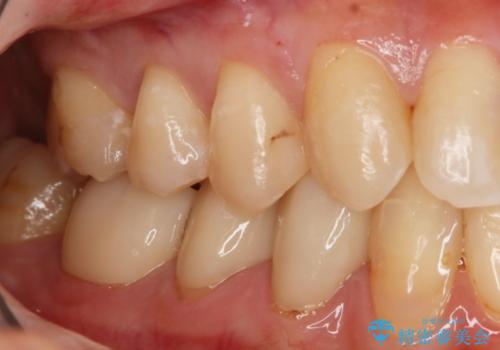

- 以前虫歯になり保険でプラスチックの詰め物をした部分の変色を主訴に、やり直しのご依頼を頂きました。

各治療法のメリット/デメリットをご説明させていただき、自費治療のセラミックインレーをご選択いただきました。

インレー治療は来院回数2回程で終了する虫歯の治療で、削る範囲も必要なエリアだけに限定できるためなるべくご自身の歯を残したい方に最適です。